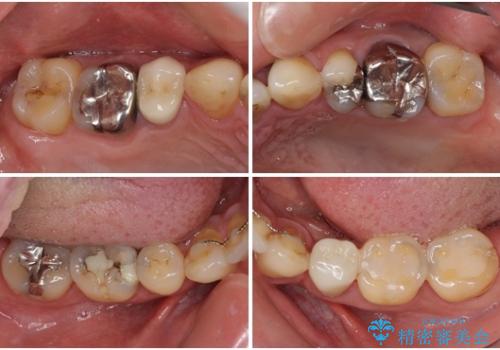

- むし歯による奥歯の痛みを気にして来院された患者様です。

神経にまでむし歯の及んでいる歯や、既に根管治療がされている歯に痛みがあったため、まずは根管治療を行うこととしました。

その後、以前行った抜歯矯正の後戻りをインビザライン・ライトにより改善し、むし歯や銀歯はオールセラミッククラウンにて補綴治療することとしました。